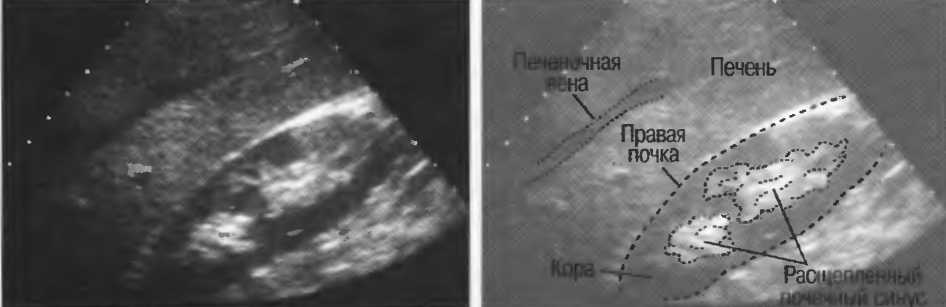

4. У здоровых обследуемых паренхима печени должна быть немного более эхогенна. чем кора рядом расположенной почки (рис. 26).

Рис.26. Продольный срез через печень и правую почку: нормальная паренхима печени более эхогенна, чем паренхима нормальной почки. Это еще один способ проверки качества изображения.